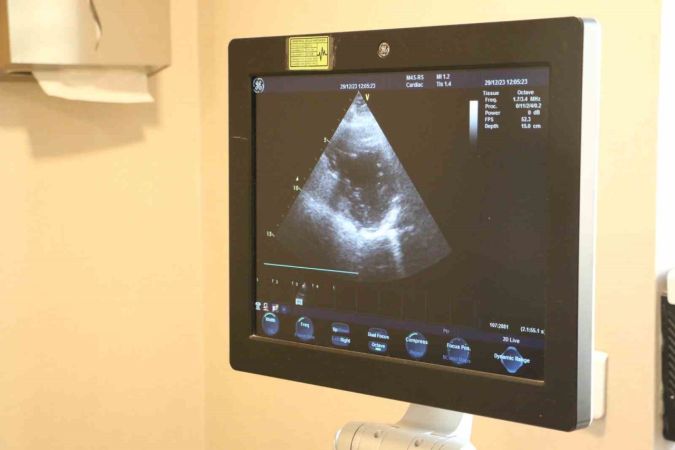

"Kalp kapak hastalıkları, kalp kapaklarının işlevini kaybetmesiyle ortaya çıkar. Zamanla yaşa bağlı olarak gelişebilir, enfeksiyon, travma ya da kalp krizi sonrasında da görülebilir. Kalp kapak hastalıklarının belirtileri, günlük yaşamı etkileyebilir ve ciddi sağlık sorunlarına yol açabilir."